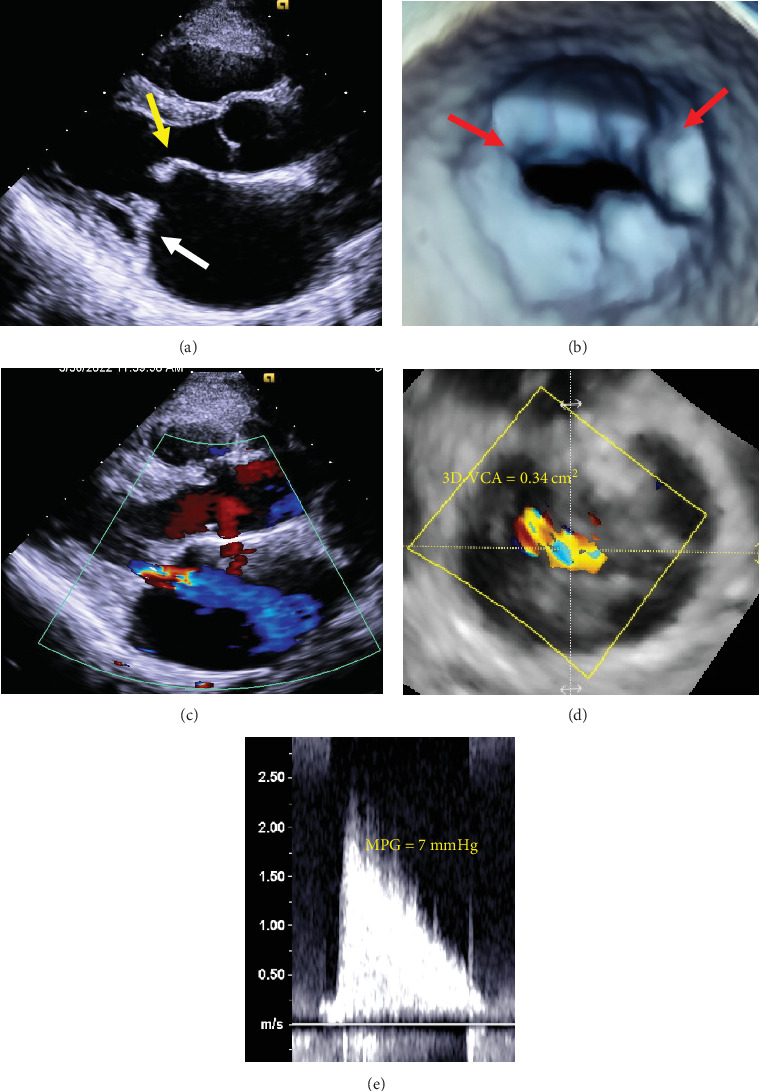

Papillary muscle rupture is a rare but serious complication during percutaneous transvenous mitral commissurotomy (PTMC). In many cases, it leads to acute significant mitral regurgitation (MR), requiring urgent surgical repair. We performed PTMC for a 49-year-old woman with symptomatic moderate rheumatic mitral stenosis. Initial balloon inflation resulted in papillary muscle rupture; however, it did not induce leaflet prolapse and worsening of MR. Finally, we succeeded in achieving a mean pressure gradient of less than 5 mmHg without worsening of MR through several balloon inflations. We experienced a rare case where papillary muscle rupture occurred during PTMC, but there was no development of acute significant MR, and salvage surgery was not required.